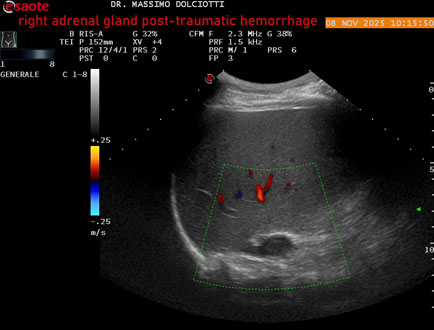

Data inserimento: 10/11/2025

Ecografia del: 08/11/2025

Strumento: Esaote MyLab Eight

Sonda: Convex Multifrequenza 1-8 MHz

Età Paziente: M 49 anni

Motivazione dell'esame: follow up per emorragia al surrene destro post-traumatica (incidente stradale).

Commento all'esame: le immagini ed il video documentano in sede surrenalica destra, formazione ipo-anecogena, a margini definiti, ovalare, delle dimensioni di 38,6 x 19,7 mm, da ricondurre ad emorragia post-traumatica.

Conclusioni: emorragia post-traumatica al surrene destro (post-traumatic hemorrhage to the right adrenal gland).

Presentazione: Dr. Massimo Dolciotti - Ancona

Elaborazione digitale: Andrea Dini - Ancona